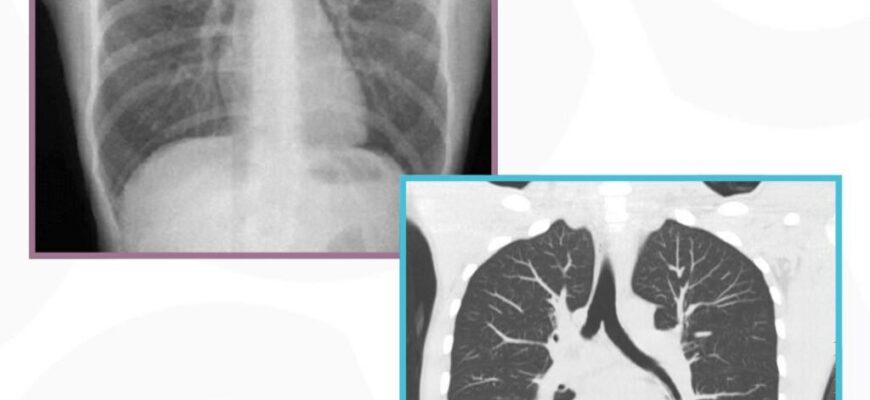

Рентгеноскопія і рентгенографія: різниця між цими методами діагностики часто залишається не зрозумілою для більшості пацієнтів. Обидва методи використовують рентгенівське випромінювання, але підходять до задачі дещо інакше, маючи свої плюси та мінуси.

Рентгенографія, у свою чергу, забезпечує статичні знімки окремих частин тіла. Це метод, до якого ми всі звикли — знімок руки чи ноги, на якому можна чітко побачити кісткові структури та можливі переломи. Він є стандартним діагностичним процедурним інструментом у медицині вже понад століття. Як сімейний альбом, тільки для ваших кісток.